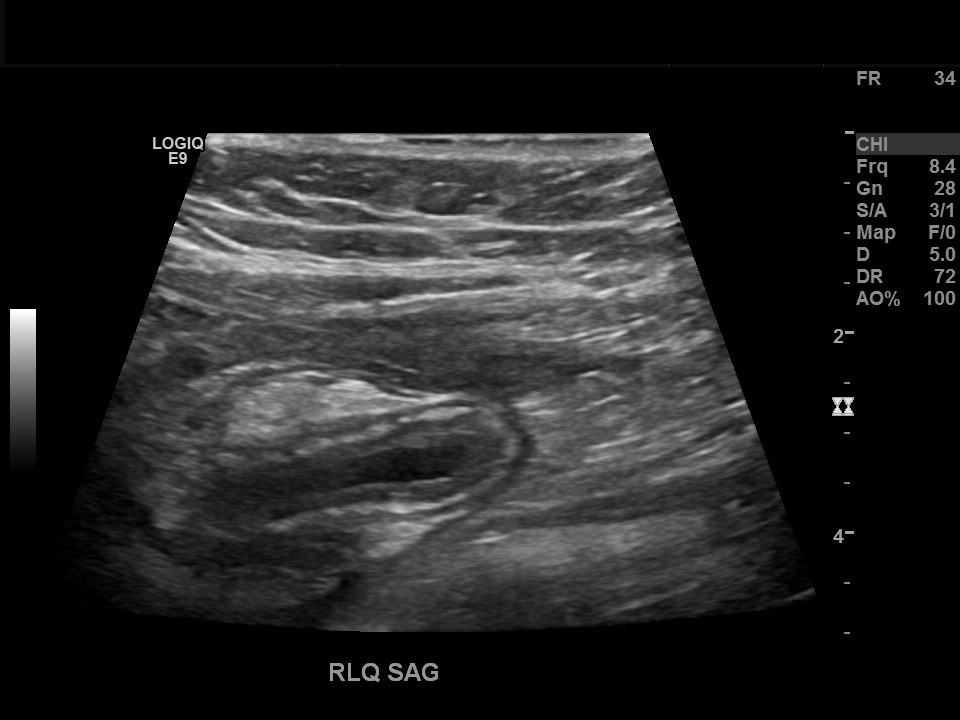

Appendicitis 19

Perforate appendicitis measuring 1.8 cm with interval abscess formation on follow up ultrasound imaging.